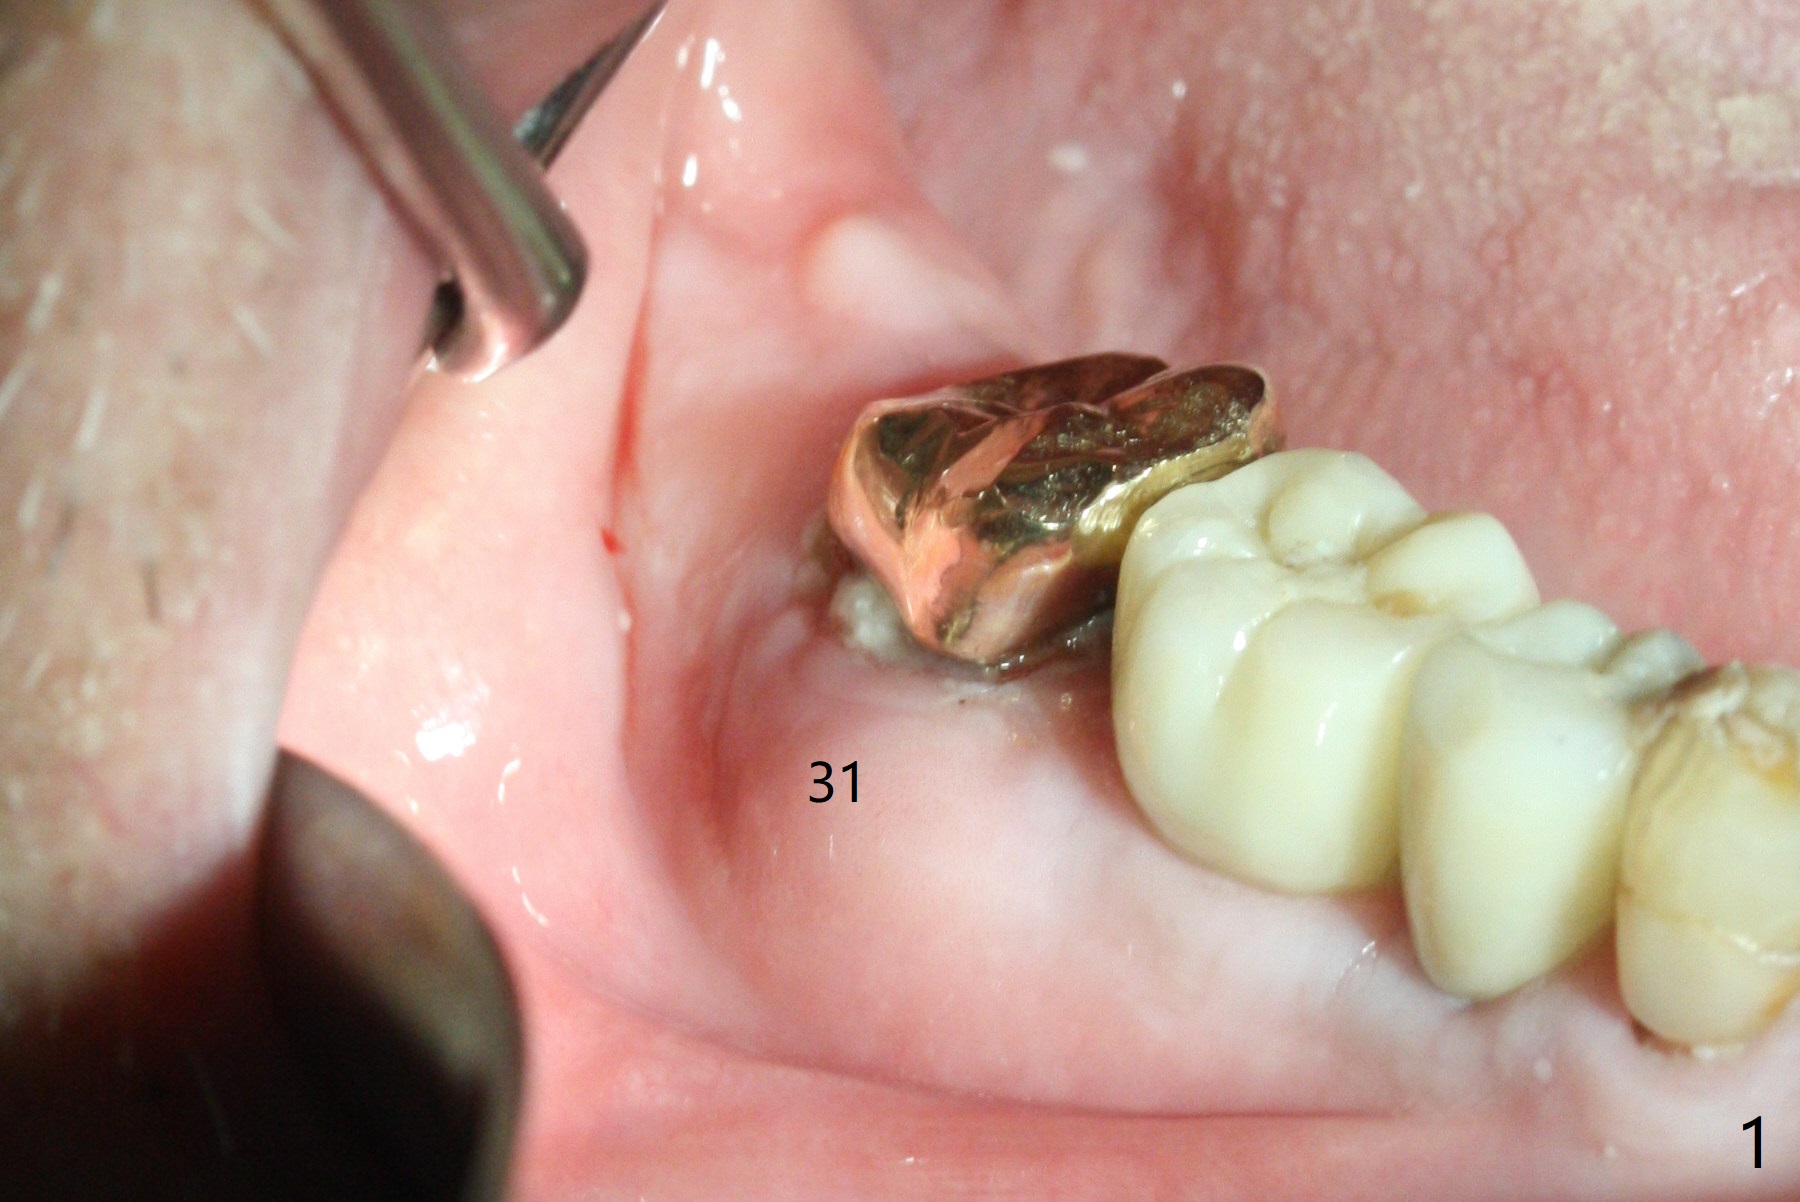

A 88-year-old man returns with pain and swelling (Fig.1), one year after diagnosis of #31 mesial root fracture. After discussion, the tooth is extracted with socket preservation (Vanilla graft mixed with Osteogen, covered with Osteogen plug and Collagen plug, Fig.2,3). The buccal crest is much lower than the lingual one. The socket opening reduces with resolution of 4-0 Chromic gut suture 1 week postop (Fig.4). The wound is wider with foul odor 2 weeks postop (data not shown). The socket and ridge shrink with loss of the bone graft 3 weeks postop (Fig.5). The bone volume reduces with buccal plate collapse 3 months postop (Fig.6,7). Immediate implant and provisional should be able to help restore the lost buccal plate. The buccal plate remains concave 5 months postop (Fig.8,9). The coronal section shows that there is space (Fig.10 *) buccal to the graft (G). A 2.0 mm pilot drill is used to create an initial osteotomy through the graft zone and in the beginning of the native bone (Fig.11,12). Use bone expanders (Fig.13 E) to push (arrowheads) and condense the graft bone and close the buccal gap. The apical portion of the osteotomy requires regular drills (Fig.14 D).